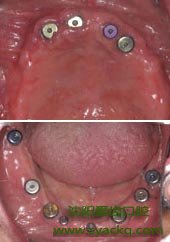

2、受植区周围软组织无严重的炎症医学教|育网搜集整理。

3、拟拔除患牙根尖区无急性炎症和大量的肉芽组织。

4、受植区周围有足够的软组织,术创能无张力关闭。 >>>>>>>>>>>>推荐阅读:西宁妇科早孕有点

5、受植区牙槽骨无明显的缺损和骨折,足以支持植入的种植体获得良好的初期机械稳定性。

6、受植区周围组织或牙齿没有其他不稳定因素,如未控制的牙周炎、根尖炎等。牙痛